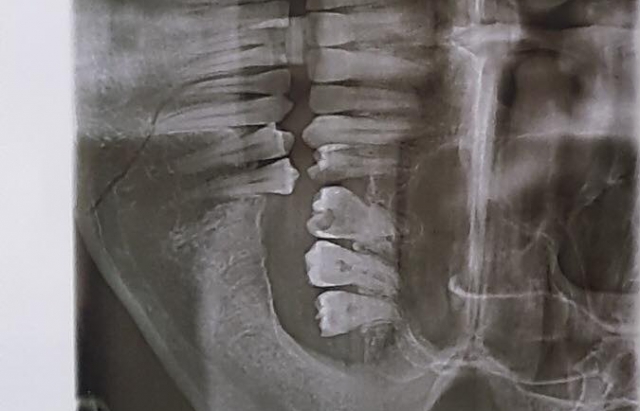

Медики діагностували у потерпілого переломом щелепи, забій волосистої частини голови і травми м'яких тканин голови.